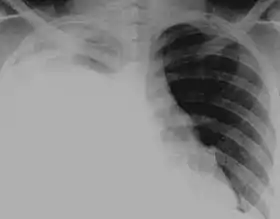

مَوَه الصَّدر[1][2] (بالإنجليزية: Hydrothorax) أَو الاستشقاء الصَّدري[1]، هوَ أحد أنواع الانصباب الجَنبي الذي يتراكم فيه السائل المَصلي في التجويف الجَنبي، وَمنَّ المُمكن أن يَكون مُرتبطاً بالتشمع الكَبدي المَصحوب بالاستسقاء البطني، حيثُ تتسرب السوائل المُتجمعة في جوف الصفاق إلى التَجويف الجَنبي، وَيُعتبر موه الكَبد من الأمراض صَعبة السَيطرة والتي تُؤدي بالنهاية إلى فَشل الكَبد المَصحوب بفشل بالعِلاج.[3]